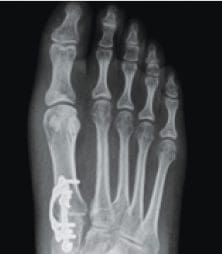

Lapiplasty® 3D Bunion Correction™ is a patented, cutting-edge procedure designed to correct the full 3-dimensional deformity rather than just removing the bump. By addressing the unstable joint and restoring the bone to its proper anatomical position, this procedure provides a more stable, lasting correction with faster recovery and improved function.

Unlike traditional bunion surgery that cuts and shifts the bone, Lapiplasty® uses advanced, precision instruments to rotate the entire deviated bone back into alignment. Titanium plating technology then secures the correction at the root of the deformity, stabilizing the joint and helping prevent recurrence.